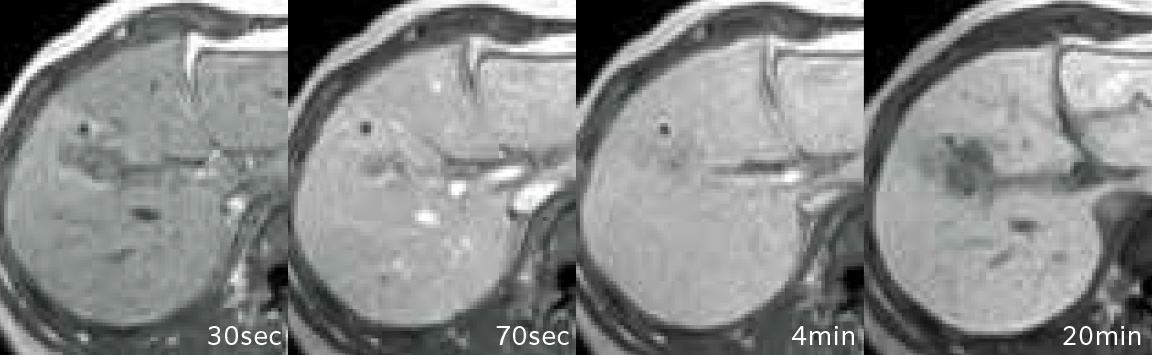

2D-RSSG Dynamic EOB